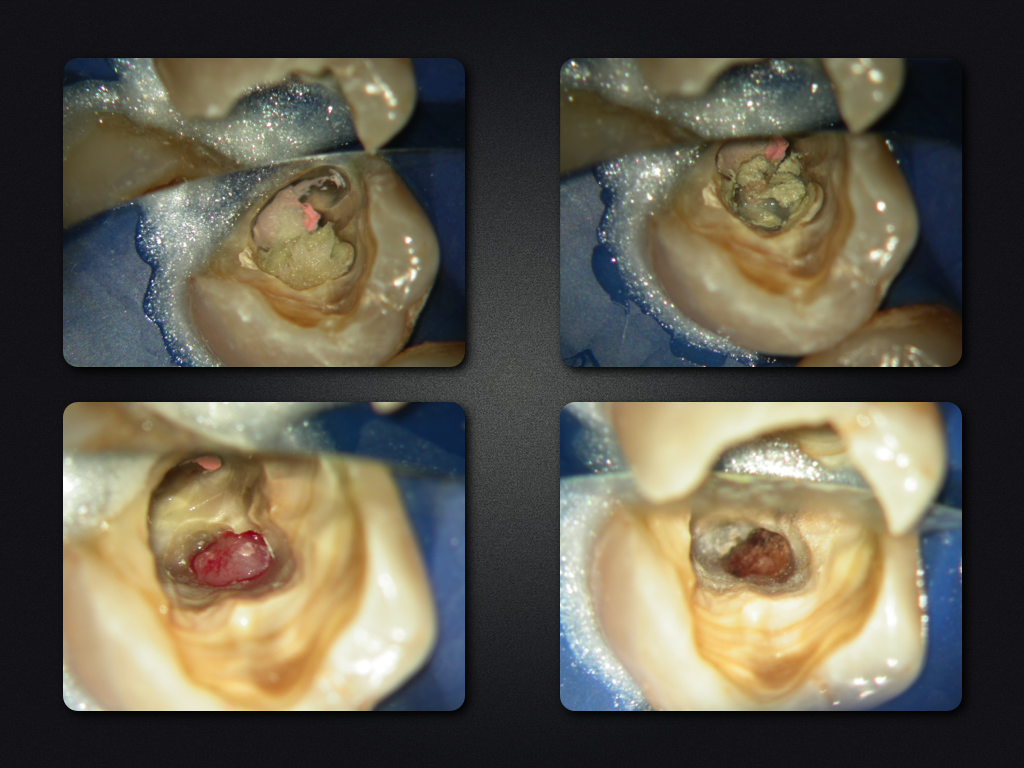

35D.005

2D zuzüglich 3D (V)